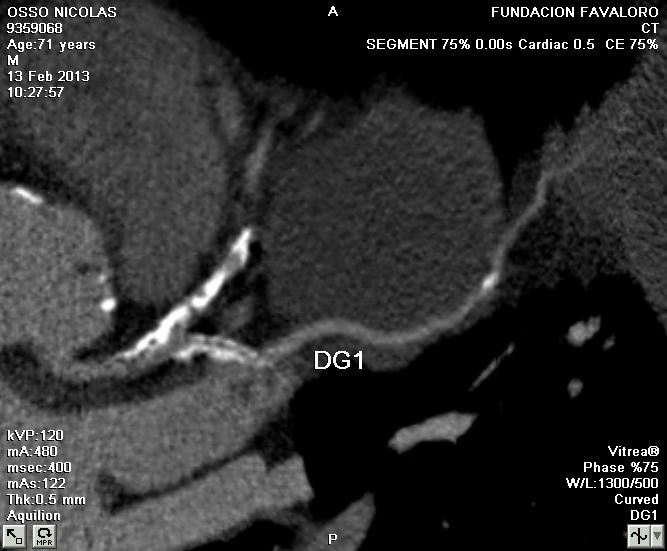

The patient was discharged the next day taking aspirin and prasugrel. At 6 months, the patient was asymptomatic with normal perfusion and a multi-slice CT Scan showed that LAD aneurysm was closed and that the stents were patent (Figure 9, Figure 10)